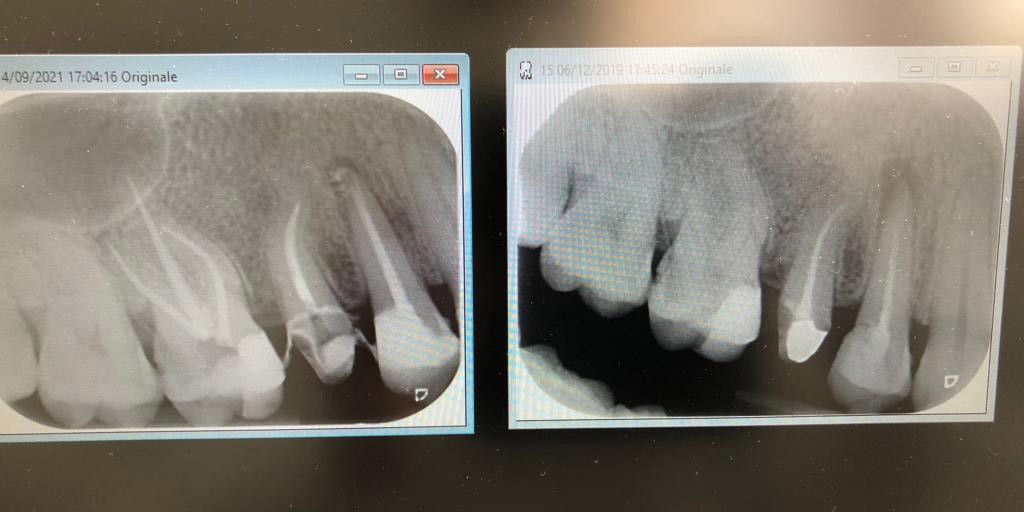

Nell'immagine precendete possiamo vedere a destra profonda carie del molare e infezione apicale del primo premolare, mentre a sinistra devitalizzazione del molare e ritrattamento del premolare